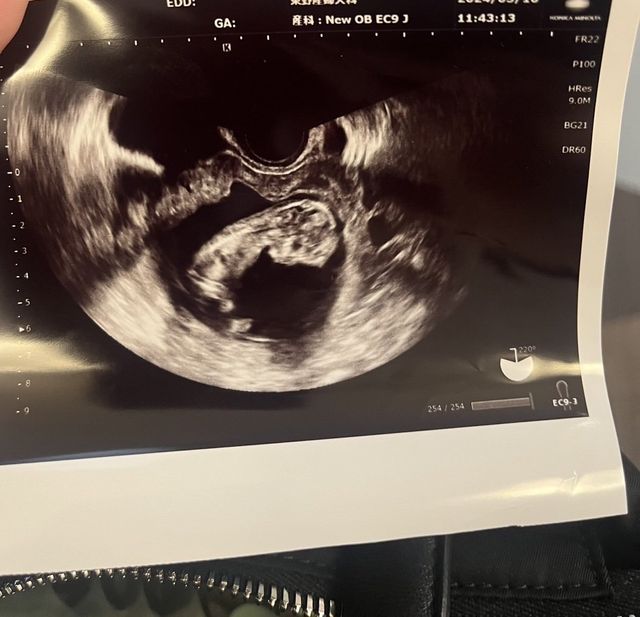

한일부부 입니다. 작년에 8월에 처음 임신됬을때 초기에 자연 유산 후 현재는 14주쯤 됬네요. 아직 성별은 모르지만 잘 키워보겠습니다. 이름도 정해야되네요ㅎㅎ